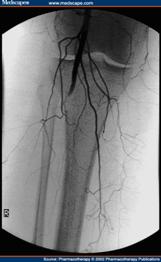

A. 動脈攝影:可查出血管阻塞之部位及阻塞之程度,於決定是否進行血管重建手術時,此為一必要之例行性檢查。

D. 血管腔內支架放置手術:以特殊的導管進入病人血管內,在精密的血管攝影輔助下,以各種導線或動脈血管擴張氣或置放血管內支架來打開嚴重狹窄或阻塞的血管。在精密的血管攝影輔助下,以各種導線或動脈 血管擴張氣或置放血管內支架來打開嚴重狹窄或阻塞的血管。 血管內支架手術的作法是在局部或是區域麻醉方式下,由病人的大腿經由一個小傷口,以特殊的導管進入病人血管內,在精密的血管攝影輔助下,以各種導線或動脈血管擴張氣球打通阻塞的血管,之後再置入適當尺寸及長度的血管內支架來維持血流的暢通,使得原本缺少動脈血流的遠端血管得到血流的再灌注,達成治療目的。由於血管阻塞複雜程度因人而異,血管腔內介入性手術不一定能夠解除所有的問題。 因醫師純熟的技術及醫療儀器科技化,已將併發症之發生減至最低。但有些病人仍有可能無法保住壞死的肢體。由於不用放置人工血管,所以手術範圍小,沒有傳統手術過後肢體腫脹的問題。因為所有的治療都在血管內完成,不用作血管的縫合,也大大地縮短了手術時間和術後諸如感染、出血等併發症的可能性。 一般傳統的血管繞道手術,在手術之後可能需要住院一個星期至兩個星期的時間才能出院,由於手術的時間長、範圍廣,再加上肢體需要一段時間來適應人工血管,所以患肢通常是在一、兩個月以後才完全復原。如果單純以血管內支架手術就得以治療的周邊動脈血管阻塞性疾病,通常在治療後就可以馬上下床活動,一至三天就得以出院,對於日常生活及活動影響極小。

E. 血管攝影及血管腔內介入性手術:解決血管狹窄或阻塞,恢復組織灌流,減少或解除組織缺血症。 解決血管狹窄或阻塞,主要效益是恢復組織灌流,減少或解除組織缺血症。以避免組織壞死或截肢等問題。 一般而言,90%以上的病人可以獲得改善。

其主要是利用高壓性的小氣球來打開阻塞的血管,或置放血管內支架來打開嚴重狹窄或阻塞的血管。 一般施行經皮血管內整形術只需局部麻醉並於手術室中進行,通常會將導管插入血管內,達正確位置後,注射顯影劑。 依血管病變程度醫師會決定是否執行氣球擴張術或裝置血管支架。整個手術治療約需1至3個小時,結束時即將全部導管拔除,傷口處直接加壓,直到確定沒有出血現象後,覆蓋無菌紗布,並以沙袋繼續加壓止血。